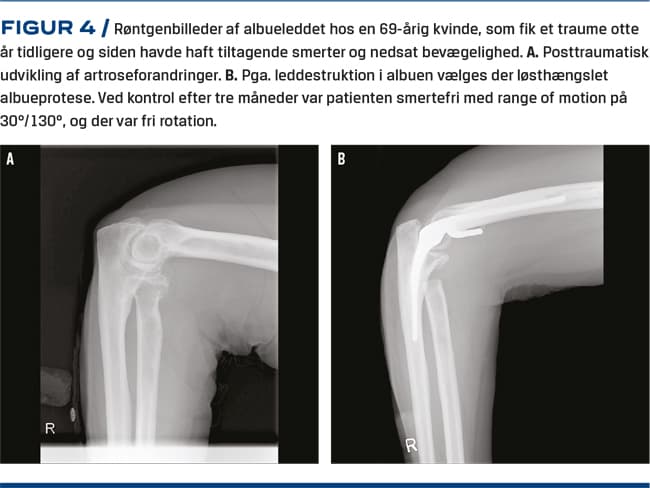

Albueartrose

Albueartrose er ofte sekundær til tidligere traumer. Primær albueartrose er en sjælden tilstand med en prævalens på < 2%. Den forekommer hyppigst hos midaldrende mænd i den dominante albue [5]. Tilstanden kan dog ses i alle aldre og hos begge køn og ses i tiltagende grad hos sportsudøvere med betydelig albuebelastning [6]. Tidligere var den hyppigste årsag til indsættelse af en albuealloplastik reumatoid artritis, men på baggrund af bedret medicinsk behandling er dette helt ændret [7]. Nu behandles flest patienter med albuealloplastik pga. primær og posttraumatisk artrose samt frisk fraktur [8]. Der indsættes samlet ca. 100 albuealloplastikker årligt i Danmark, og behandlingerne er samlet på få specialiserede afdelinger.

Artrose i albuen kan behandles med artroskopisk eller åben led-løsning med synovektomi, løsning af kapsel og resektion af osseøse prominenser herunder caput radii og ledmus. Herved kan bevægelighed, smerter og aflåsninger bedres. I degenerative led er bedringen oftest forbigående, men kan udskyde tidspunktet for alloplastik. Prognosen ved isolerede bløddelskontrakturer er betydeligt bedre. Ved fremskredne tilfælde med symptomer fra n. ulnaris giver åben kirurgi mulighed for samtidig in situ-løsning af n. ulnaris. Ellers er resultaterne for åben og skopisk operation sammenlignelige [6, 26]. Efterbehandlingen er hurtig guidet mobilisering evt. med passiv udstrækning [6, 26]. Ved svær artrose, hvor andre behandlingstilbud har fejlet, kan albuealloplastik tilbydes [6, 8, 27]. Der findes forskellige alloplastiktyper, der anvendes på forskellige indikationer [8, 27]. Den løst hængslede totalalloplastik er den mest anvendte og fremviser de bedste resultater ved artrose (Figur 4) [7, 27, 28]. Efterbehandling er oftest kort immobilisering i bandage, efterfulgt af fri guidet mobilisering. 90% oplever lindring af smerterne, men må acceptere vægtrestriktion for ekstremiteten. Tiårsproteseoverlevelsen er i europæiske studier 80-85% [8, 27, 28]. Proteseløsning, fraktur, dyb infektion og n. ulnaris-påvirkning er de hyppigste komplikationer, der ses i op til 20% af tilfældene [8, 29, 30].